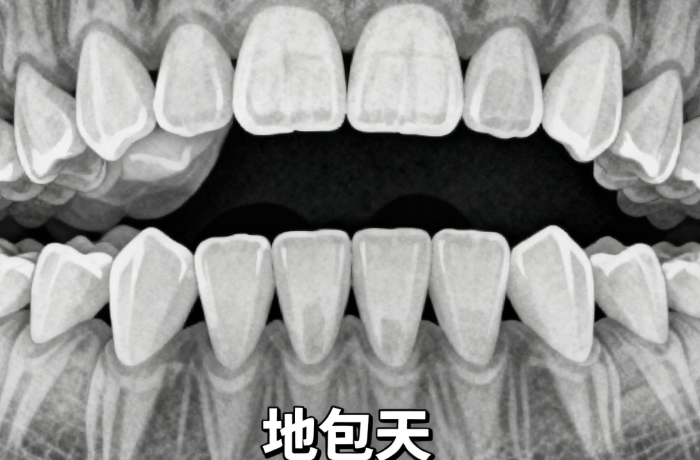

你是否正在为牙齿矫正而烦恼,却不知道SGTB矫正器每天该戴多久才能达到理想疗效?其实,牙医列出了3个关键时间点,20小时是基础,超过22小时疗效更好。www.59w.net接下来,我们将围绕SGTB矫正器每天戴几个小时,为你详细分析不同情况下的佩戴要求、佩戴方法、注意事项以及治疗周期等内容。